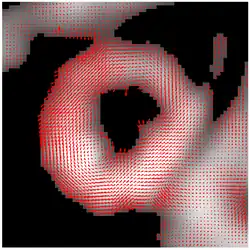

The result of HARP tracking of one frame of cardiac MRI is shown in the figure. It is obtained by calculating both motions from horizontal direction and vertical direction, resulting in a 2D vector field showing the motion of every material point on the myocardium at this time frame.

The entire HARP algorithm takes only a few minutes to perform on a normal computer and the motion tracking result is accurate (with a typical error range of pixel). As a result, it is now widely adopted by the medical image analysis community as a standard processing technique for tagged MRI.